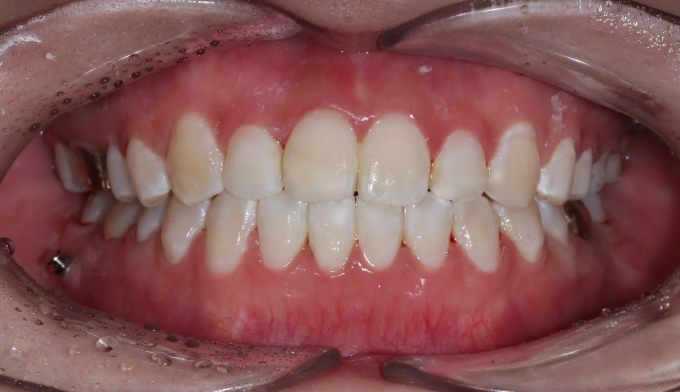

개방교합,

불규칙앞니

개방교합은 양쪽 어금니가 잘 맞닿아 있는데도 앞니가 위아래로 떠서 맞물리지 않는 경우를 말합니다.

발음도 좋지 않게 되며, 심미적으로도 좋아보이지 않습니다.

이 케이스는 앞니의 치열도 불규칙합니다.

미니스크류를 이용하여 어금니 교합을 변화시켜 개방교합을 해소하였습니다. 이와 동시에 어금니의 후상방 이동으로 앞니 배열공간을 만들었고 앞니를 가지런하게 배열시킬 수 있었습니다.

총 치료기간은 15개월 소요되었습니다.